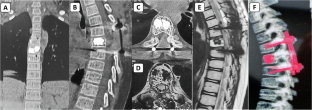

A 14-year-old boy presented with thoracic myelopathy signs. The MRI scan suggests T1 and T2 hyperintense signals within the T6 vertebral body with extramedullary extradural space occupying the lesion. The CT scan showed a “polka dot” appearance. Preoperative endovascular embolization followed by surgical decompression with posterior instrumented stabilization under O-arm navigation and tumor excision was planned. Cystic extradural lesion excised and vertebroplasty done at T6 level. Histopathology slides confirmed hemangioma.

The most common age of involvement is between 30 and 70 years it is rarely seen in the pediatric age group. To the best of our knowledge, fewer than 20 cases of pediatric aggressive vertebral hemangiomas have been reported. Based on a review of pediatric AVH only 4 patients have been treated with preoperative vascular embolization followed by surgical decompression and stabilization. O-arm navigated AVH excision and vertebroplasty has never been described in the literature; this being the first case. It also aids in the identification of tumor margins along with real-time monitoring of adequate resection.